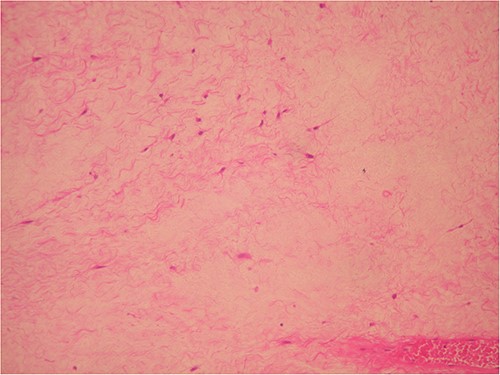

The surgically extracted in the toto mass was oval-shaped with a myxoid appearance, soft during palpation and yellowish in apperance. It was 3.2 cm at its greatest diameter. The mass was histologically and immunohistochemically examined (Figs 3–5). The tumor was severely hypocellular and consisted of stellate and spindle cells without atypia or mitosis, in an abundant myxoid stroma. Immunohistochemically, the tumor cells were positive for vimentin and CD34 but negative for SMA and S100. Based on these findings, a myxoma diagnosis was made.

Severe hypocellular tumors. Stellate and spindle cells in abundant myxoid stroma (H & E ×100).